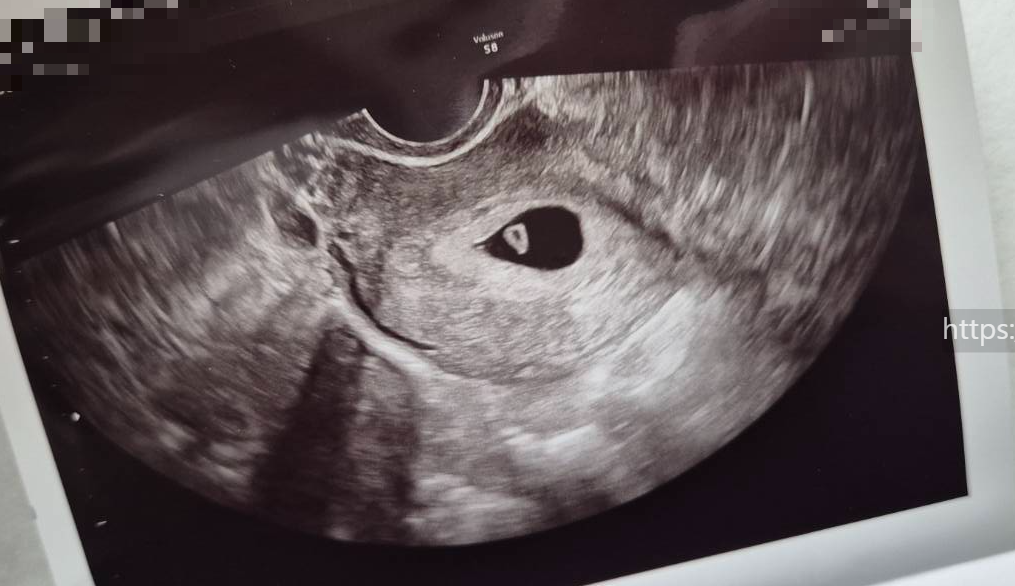

3. 초음파 확인

오늘도 역시나 진료실에 들어가자마자 초음파실로 향했다.

아기집을 본 이후로는 뭔가 초음파 볼 때 두근두근 하는 것 같다.

잘 자랐으려나.

옷을 갈아 입고 나오니

진료실 책상에 보이는 초음파 사진들!

지난주엔 없던 무언가가 아기집 안에 생겼다.

신기신기! 왕신기!

아직 아가는 아주 작지만, 난황이 아주 예쁘게 있어서 한결 마음이 편해졌다

피비침도 초음파상 문제가 없어서 괜찮을거라고

원장선생님이 대수롭지 않게 얘기해주셔서 오히려 안심이 되었다.